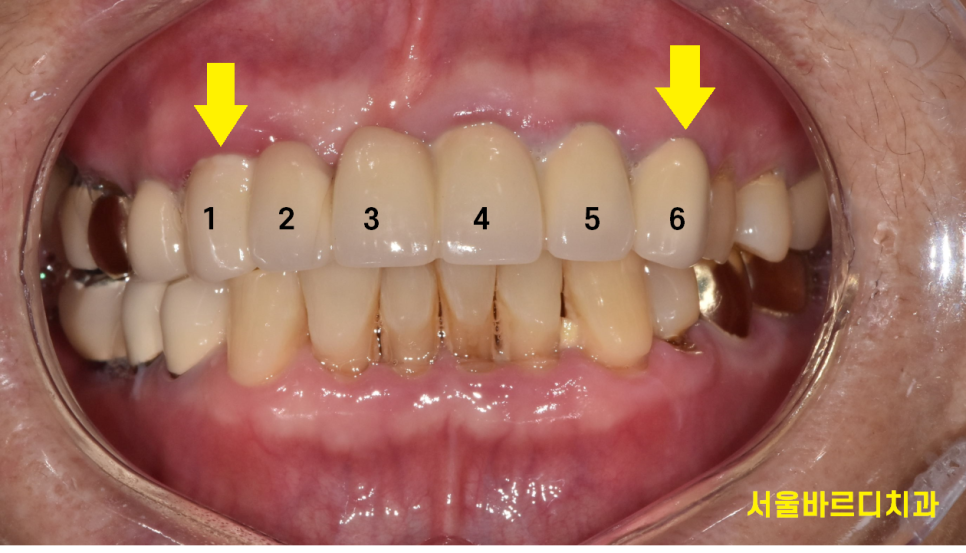

아래 앞니는 자연치아이고

위에 치아 6개를 보철하신 상태네요~

송곳니부터 송곳니까지요.

240731

4월에 수술을 하고 3개월정도 지나

머리를 만들어 드렸는데요.

똑같이 6개를 묶은 앞니 브릿지 형태인데

임플란트는 3개를 심어 6개로 만들어 드렸습니다.